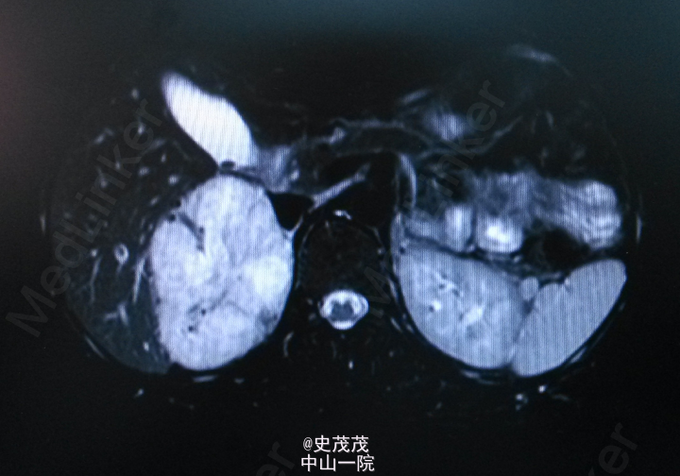

体格检查:心、肺(-)。腹平软,未见胃肠型及蠕动波。无压痛、反跳痛,未及腹部包块。肝脾肋下未及,Murphys’s sign (-),双中上输尿管点无压痛,肝、肾区无叩击痛,移动性浊音阴性。双肾区不饱满,肋腰凹存在,双肾未触及,为问及肾血管性杂音。双肾区、左侧输尿管行程区压叩痛(-)。膀胱区不膨隆,无压痛,叩诊鼓音,外生殖器无异常。 辅助检查:腹部B超示肝肾间隙范围约83×64mm低回声,边界请。彩色多普勒见血流信号。 腹部MR示右肾上腺区占位,约6.7cm×8.1cm×8.5cm大小,呈稍长T1、长T2信号,内部信号不均匀,可见斑片状明显长T1、明显长T2信号坏死区,DWI序列呈稍高信号,反相位肿块信号不减低。增强扫描,肿块呈明显不均匀强化,内部坏死区不强化,有渐进强化特征。考虑嗜铬细胞瘤可能。